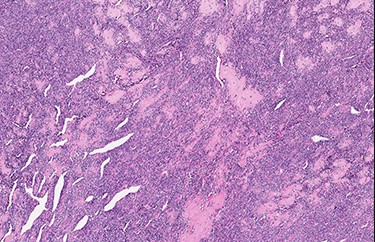

An excisional biopsy of the orbital mass was performed. We found a firm, whitish nodule that measured 2.8 × 1.9 × 1.7 cm. Microscopically, the neoplasm had a typical biphasic pattern, with a hypercellular small round cell component intermixed with islands of well-differentiated cartilage showing metaplastic bone ossification. There was an abrupt transition between the two different components of the neoplasm, and a hemangiopericytoma-like vascular pattern was noted (Figs 2–4). Immunohistochemically, the mesenchymal small cell component showed focal cytoplasmic positivity for CD99, while the cartilaginous component was S100 protein-positive (Figs 5 and 6). The neoplastic cells showed negativity for cytokeratin AE1/AE3, STAT6 (signal transducer and activator of transcription-6), CD31 and CD34. The findings were consistent with MCS. This case was sent for a second opinion to Prof. Angelo Paolo Dei Tos (Department of Pathology, Azienda ULSS 2 Marca Trevigiana, Treviso, Italy) who confirmed the diagnosis of MCS, also reporting nuclear positivity for SOX9, a master regulator of the differentiation of mesenchymal cells into chondrocytes.

Typical hemangiopericytoma-like vascular pattern (H&E, high power view).